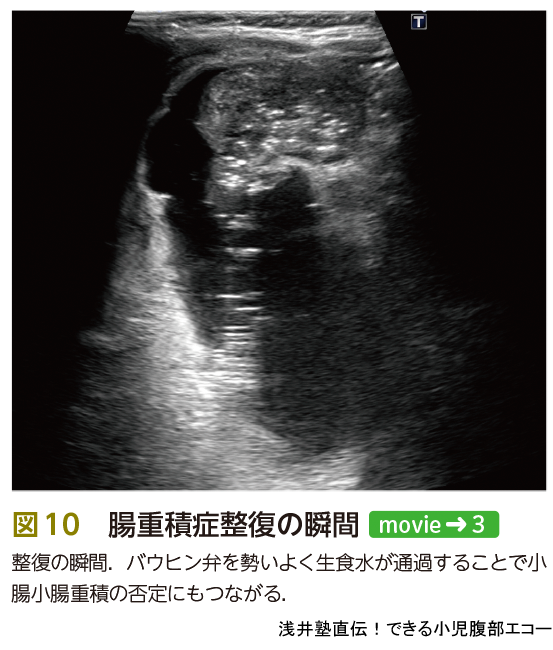

被曝がない,場所を問わない,生理食塩水を注入するために先進部病変の発見が容易になる,穿孔の際に発見が容易…,などいろいろなメリットがあるエコー整復ですが,いまだに浸透していないのが現状です.その理由の1つとして,整復の瞬間を見落とすことが怖いという意見がありました.これは大丈夫です.見落としても整復後のサイン(図11)を確認すれば,その証明になります.重積部が通過した後の肥厚したバウヒン弁は,カニの爪という意味でcrab-claw signとよばれていますが,私は勝手に「勝利のピースサイン」とよんでいます(図11A).また,整復後の肥厚した回腸末端の短軸像をpost-reduction doughnut signとよびます(図11C).生理食塩水で充満した小腸はhoneycomb sign(図11D)とよばれ,重積が解除されてそこまで生理食塩水が到達したことを示します.小腸小腸重積が残存している場合もあるため,最後のhoneycomb signは重要です.また,バウヒン弁を通過する生理食塩水の勢いも口側に小腸小腸重積,つまり通過障害があるかどうかを判断する情報になります.

いかがでしょうか? 整復の瞬間を見落としてもエコーで整復後のサインを確認できますので,大丈夫なんです.読者の皆様がエコー整復をひろめてくれることを期待します.